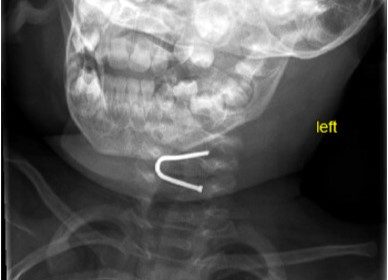

Baby gets giant nail stuck in throat and has NO symptoms

Doctors in New York removed a giant U-shaped nail from a 13-month-old…